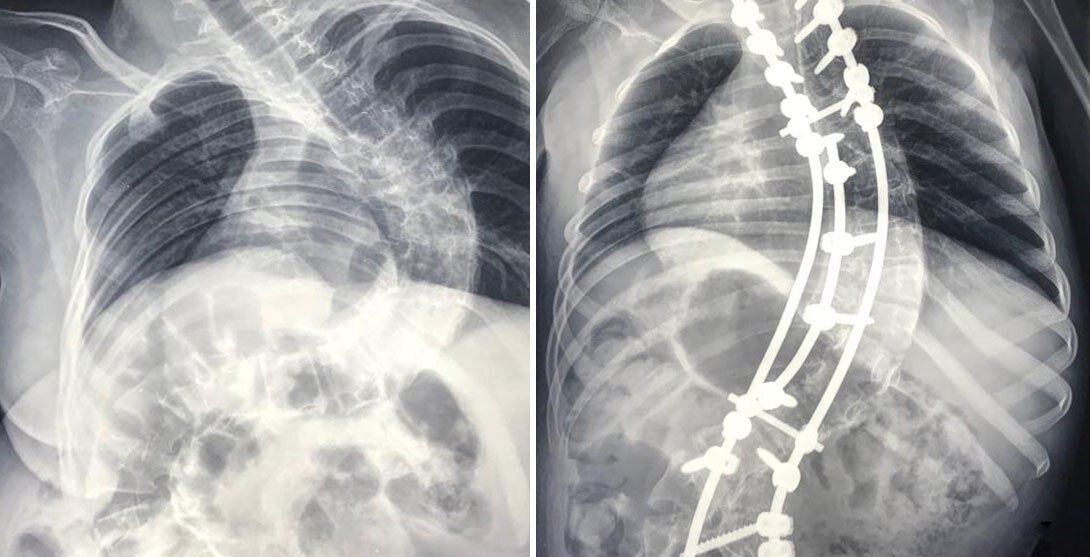

В предыдущей статье я уже писала, что моя дочь родилась с гипоксией, было поражение ЦНС, и ряд сопутствующих проблем. Неделя в реанимации, полтора месяца в детской больнице. Основной нашей проблемой был очень выраженный гипотонус (слабые мышцы). Дочка поздно начала держать голову, в год ещё не садилась. Пошла сама только в 1,8. Конечно, всё это время активно лечились: массажи, физио, уколы. Нас направляли в питерскую больницу с диагнозом «синдром Вердинга-Гофмана»: разновидность спинально-мышечной атрофии, при которой мышцы ослабевают вплоть до наступления смерти; продолжительность жизни зависит от того, когда болезнь дебютирована; при врождённой форме живут совсем мало. Диагноз ставили под вопросом, но тем не менее – в карточке был неоднократно записан. Те слова, которые я привела в заголовке, - это реальная цитата невролога. Я ни в коем случае не ругаю врачей. Всё делали правильно, что перестраховывались. Но всё-таки от поездки в Питер мы отказались (за что даже была вызвана опека

Основной нашей проблемой был очень выраженный гипотонус (слабые мышцы). Дочка поздно начала держать голову, в год ещё не садилась. Пошла сама только в 1,8. Конечно, всё это время активно лечились: массажи, физио, уколы. Нас направляли в питерскую больницу с диагнозом «синдром Вердинга-Гофмана»: разновидность спинально-мышечной атрофии, при которой мышцы ослабевают вплоть до наступления смерти; продолжительность жизни зависит от того, когда болезнь дебютирована; при врождённой форме живут совсем мало. Диагноз ставили под вопросом, но тем не менее – в карточке был неоднократно записан. Те слова, которые я привела в заголовке, - это реальная цитата невролога.

Я ни в коем случае не ругаю врачей. Всё делали правильно, что перестраховывались. Но всё-таки от поездки в Питер мы отказались (за что даже была вызвана опека – об этом я расскажу в отдельной статье))), у генетика тоже не проверялись. Конечно, надо было бы, но… Интуитивно я 99% знала, что никакого «Вердинга-Гофмана» у дочки нет. Хотя и начиталась про эту болезнь столько, что депрессию схлопотала. 1% сомнений был.

Сейчас дочке 4 года. Из проблем осталась только речевая задержка. Надеюсь, скоро справимся и с ней. Ну и лишний вес, о чём писала в предыдущей статье. В остальном – ребёнок умный, общительный, активный. Ходит в обычный детский сад. Что касается тонуса мышц – практически сильнее меня 😊 Тонус пришёл в абсолютную норму, даже чуть перегнав. Бегает, прыгает. «Физическое развитие – выше среднего», так сейчас пишут в карточке.